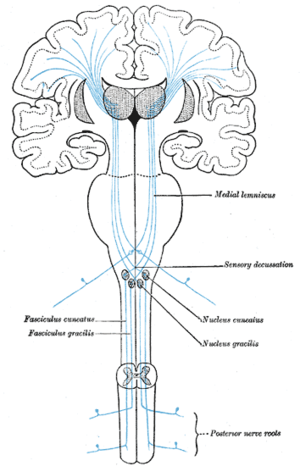

تصعد جميع معلومات اللمس / الاهتزاز الواردة إلى الحبل الشوكي عبر المسار الخلفي (الظهري) العمود الفقري الإنسي عبر النواه الرشيقة (T7 وأدناه) أو الاسفينية (T6 وما فوق). ترسل الاسفينية إشارات إلى نواة القوقعة بشكل غير مباشر عبر المادة الرمادية في العمود الفقري ، وتستخدم هذه المعلومات في تحديد ما إذا كان الصوت المدرك هو مجرد ضوضاء / تهيج الزغابات. تتقاطع جميع الألياف (يسارًا يمينًا) في النخاع.

عادةً ما يحتوي المسار الحسي الجسدي على ثلاث خلايا عصبية:[13] الدرجة الأولى والثانية والثالثة.

- العصبون من الدرجة الأولى هو نوع من العصبون وحيد القطب الكاذب وله دائمًا جسمه الخلوي في العقدة الجذرية الظهرية للعصب الشوكي مع محوار طرفي يعصب مستقبلات اللمس ومحور عصبي مركزي على العصبون من الدرجة الثانية. إذا كان المسار الحسي الجسدي في أجزاء من الرأس أو الرقبة غير مغطاة بأعصاب عنق الرحم ، فسيكون العصبون من الدرجة الأولى هي العقد العصبية الثلاثية التوائم أو العقد في الأعصاب القحفية الحسية الأخرى).

- يحتوي العصبون من الدرجة الثانية على جسم خلوي إما في النخاع الشوكي أو في جذع الدماغ. ستعبر ( تقاطع ) محاور العصبون الصاعد إلى الجانب المقابل إما في الحبل الشوكي أو في جذع الدماغ .

- في حالة اللمس وأنواع معينة من الألم ، يكون للخلايا العصبية من الدرجة الثالثة جسمها الخلوي في النواة الخلفية البطنية للمهاد وتنتهي في التلفيف خلف الفص الجداري في القشرة الحسية الجسدية الأولية (أو S1).

اللمسة الدقيقة (أو اللمسة التمييزية) هي طريقة حسية تسمح للموضوع بإحساس اللمس وتحديد موقعه. يُعرف شكل اللمس الذي لا يكون فيه التوطين ممكنًا باسم اللمس الخام (البدائي). يعد مسار العمود الخلفي - الفتيل الإنسي هو المسار المسؤول عن إرسال معلومات اللمس الدقيقة إلى القشرة المخية للدماغ.

اللمسة البدائية (الخام) (أو اللمسة غير التمييزية) هي طريقة حسية تسمح للشخص أن يشعر بأن شيئًا ما قد لمسه ، دون أن يكون قادرًا على تحديد مكان لمسه (على النقيض من "اللمسة الدقيقة"). تُحمل أليافها في السبيل النخاعي المهادي ، على عكس اللمسة الرقيقة ، التي تحملها العمود الظهري. [17] نظرًا لأن اللمسة الدقيقة تعمل عادةً بالتوازي مع اللمس الخام ، فسيكون الشخص قادرًا على تحديد مكان اللمس حتى يتم تعطيل الألياف التي تحمل لمسة ناعمة ( العمود الخلفي - مسار الفتيل الإنسي ). عندها سيشعر الشخص بلمسته ، لكنه لن يتمكن من تحديد مكان لمسه..